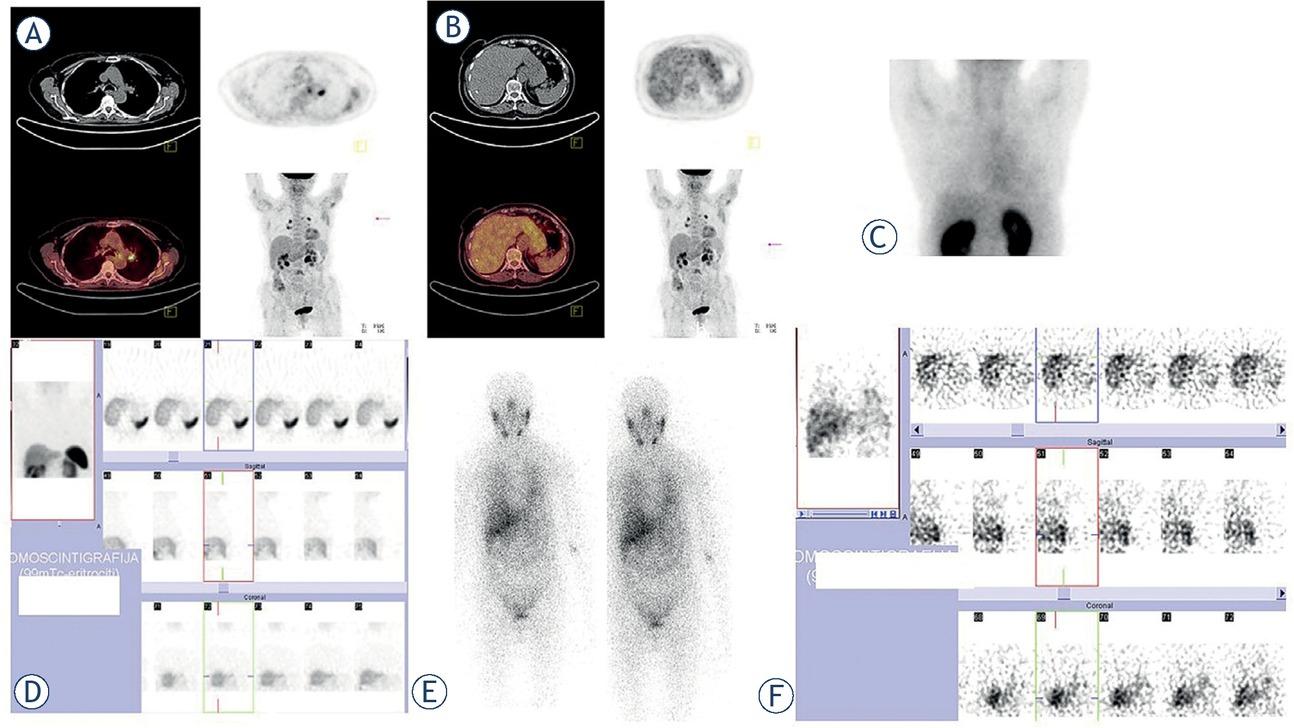

Figure 1

Figure 2

Figure 3

Figure 4